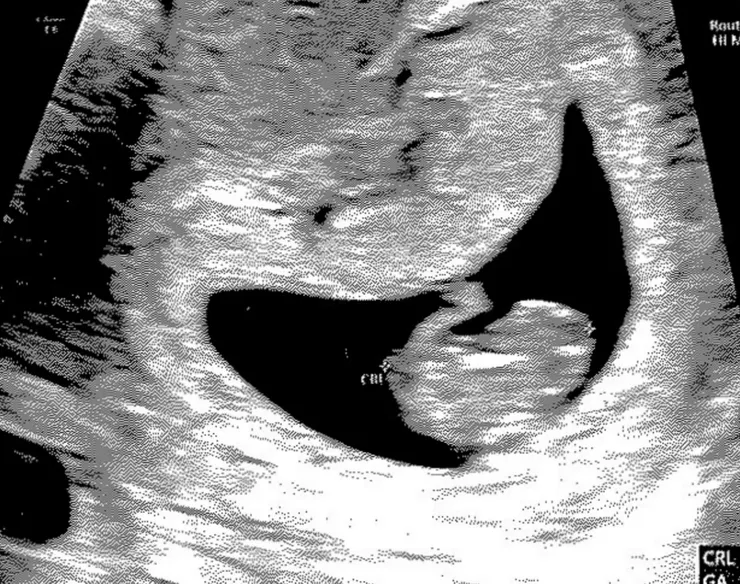

首先自己去量身高體重與血壓,接著去護理站抽號碼,等待叫號後護理師詢問什麼事,說明後請我去驗尿;驗好再抽號,叫號後護理師說確定懷孕去照超音波,照完超音波,寶寶有好好的長大,預產期也跟第一次預期的一樣,會是個蛇年寶寶,我也收到第一張超音波照。

我真的好開心、好沒有真實感,我甚至覺得超音波那團肉很可愛!